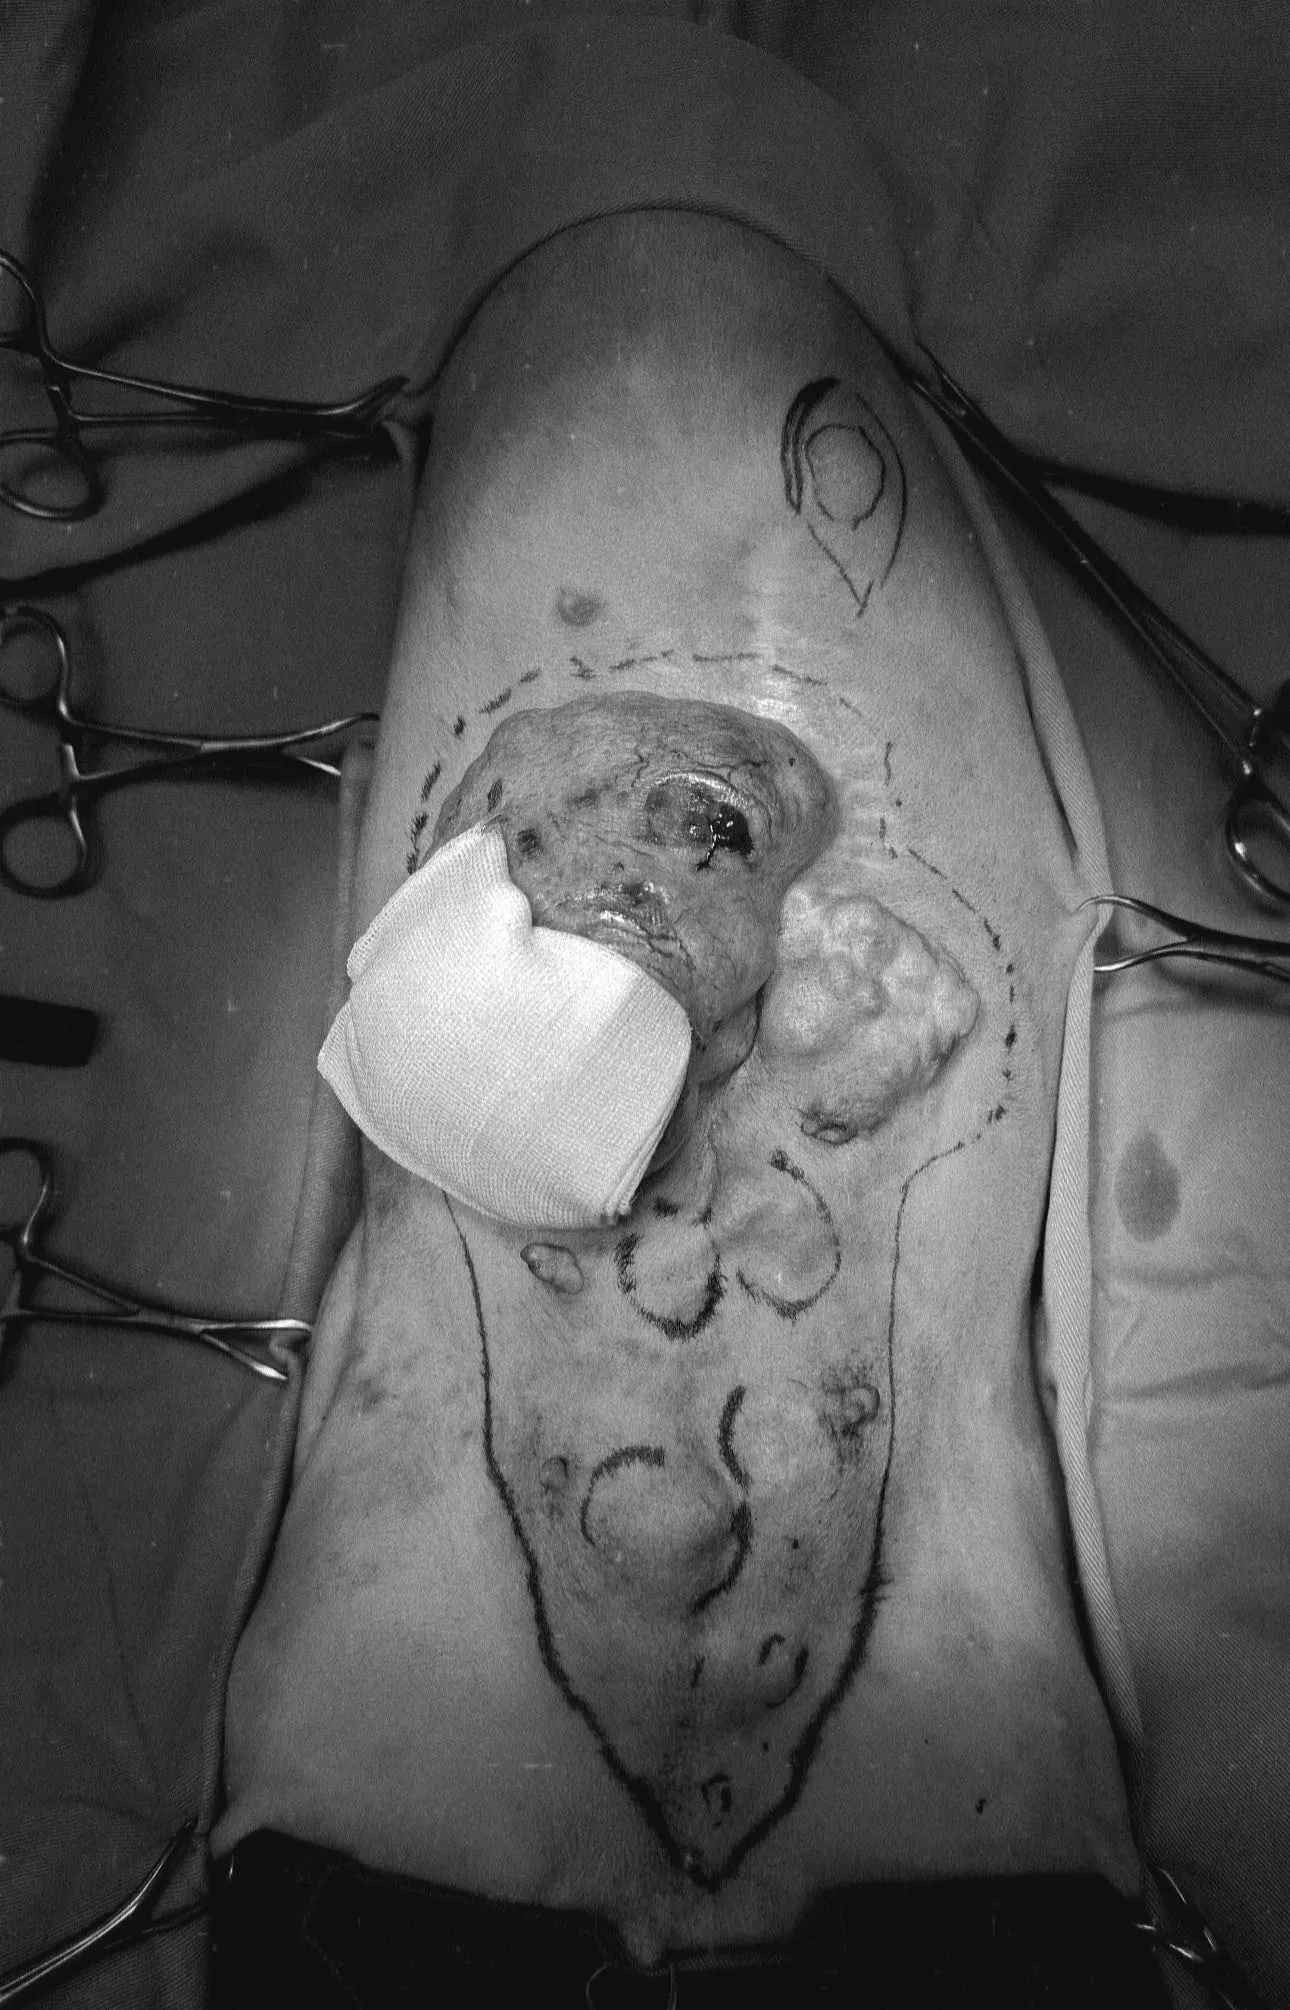

🐾 最後分享一個病例,這隻14歲的狗狗因為睪丸越來越大,快要垂到地上來就診,檢查之下不僅左邊睪丸變成腫瘤,右邊居然也有隱睪! 手術還不得不連陰囊也一起切除了(正常絕育時不需切除),切片結果是有轉移風險的惡性腫瘤,塞托利細胞瘤(Sertoli cell tumor),術後還需要持續觀察!

🐾 最後分享一個病例,這隻14歲的狗狗因為睪丸越來越大,快要垂到地上來就診,檢查之下不僅左邊睪丸變成腫瘤,右邊居然也有隱睪! 手術還不得不連陰囊也一起切除了(正常絕育時不需切除),切片結果是有轉移風險的惡性腫瘤,塞托利細胞瘤(Sertoli cell tumor),術後還需要持續觀察!